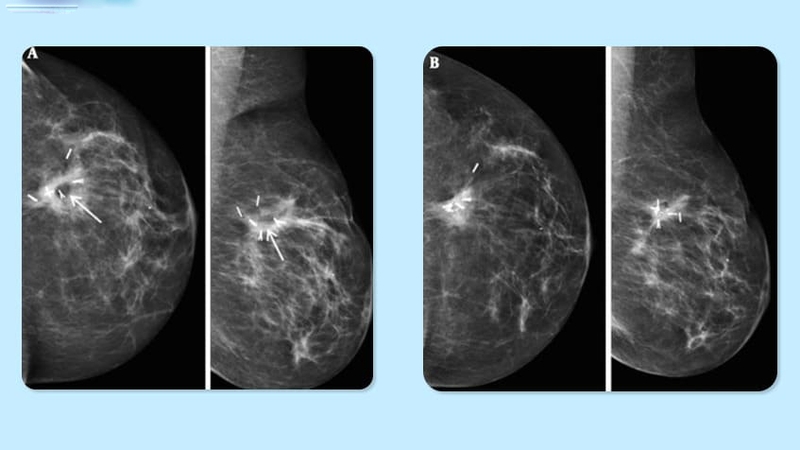

Đối với nhiều người sống sót sau ung thư vú, vi phẫu mang lại tia sáng để giúp họ lấy lại hình ảnh cơ thể thông qua việc tái tạo nhu mô vú, sử dụng mô từ chính cơ thể họ, giúp họ chữa lành cả về thể chất và tinh thần.